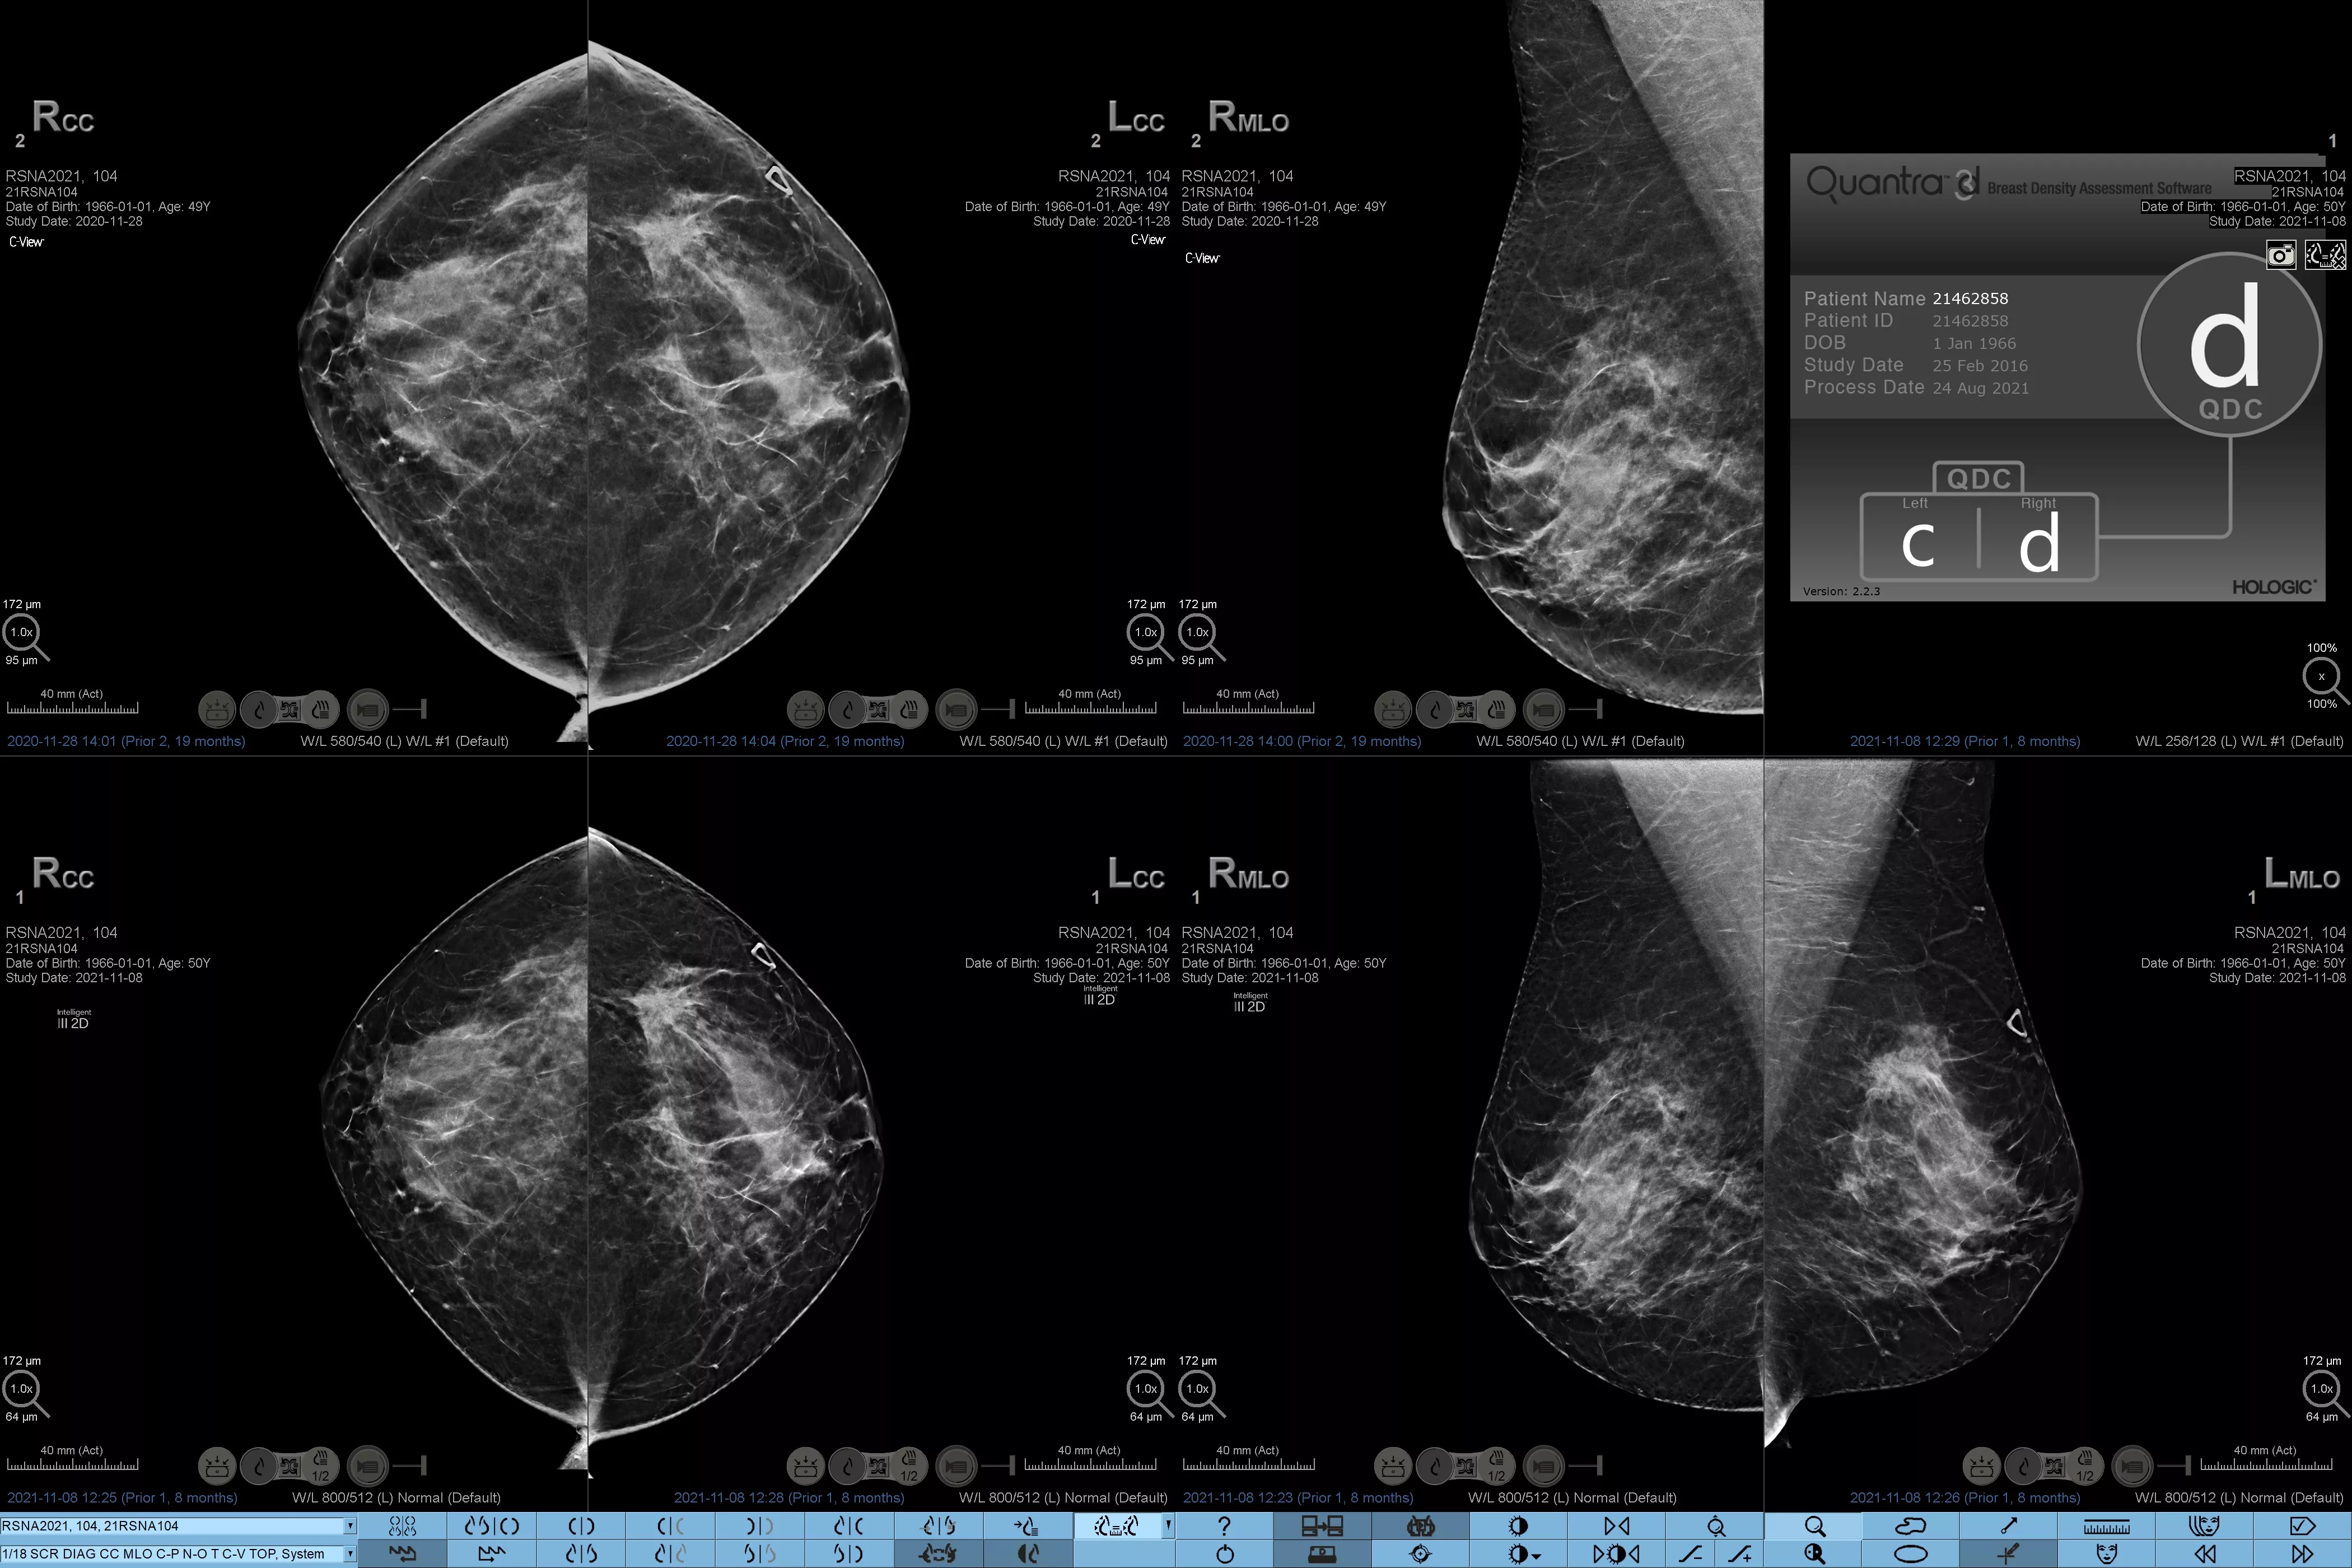

Det är känt att en hög brösttäthet ökar en kvinnas risk för bröstcancer.1 Behovet av noggrann och opartisk analys är därför kritiskt. Med hjälp av maskininlärning analyserar Quantra Technology-programvaran både 2D™- och tomosyntesbilder för fördelning och textur av parenkymal vävnad. Den kategoriserar bröst i fyra bröstkategorier utifrån sammansättning enligt riktlinje från American College of Radiology (ACR) BI-RADS Atlas 5th Edition.2

* Poängbedömningar baseras på ACR BI-RADS-kategorier enligt de reviderade riktlinjerna från American College of Radiation (ACR) BI-RADS Atlas 5th Edition. Detta motsvarar mönster och textur jämfört med volym vid bedömning av täthet.

8. Kategorier för bröstsammansättning enligt beskrivningen i ACR BI-RADS Atlas.